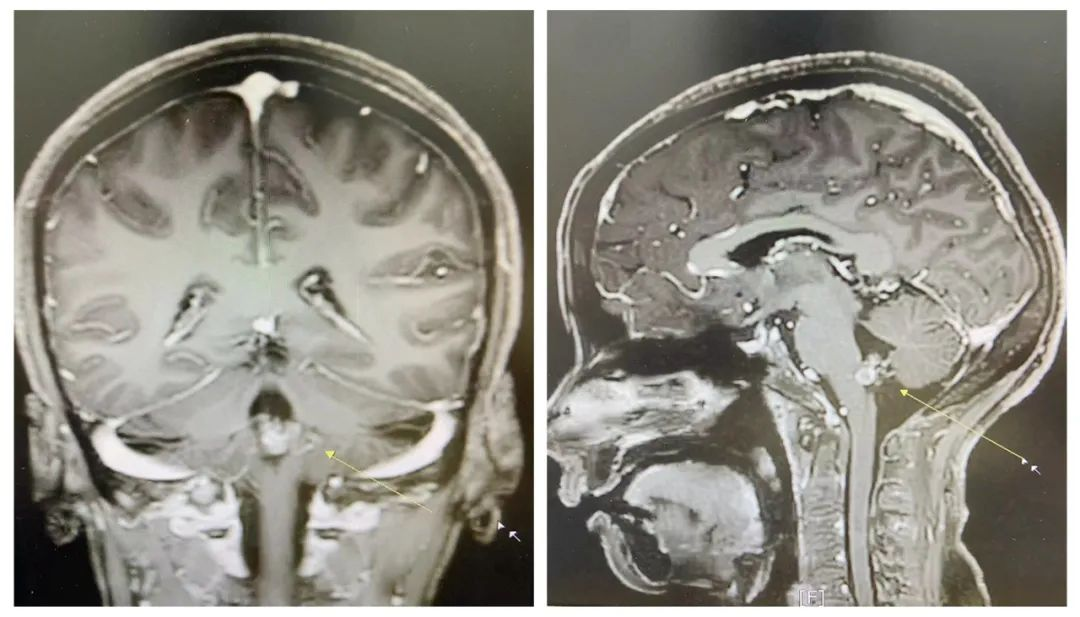

▲患者术前磁共振图片

患者陈某,女,46岁,因“突发视物晃动伴头痛”入住我院,颅脑增强MRI检查提示:延髓海绵状血管瘤。我院副院长、神经外科学科带头人王鹏及神经外科叶志其主任医师会诊,详细询问病史及翻阅检查资料后认为:患者诊断考虑延髓海绵状血管瘤合并瘤内出血。目前患者有明显临床症状,有切除手术指征。